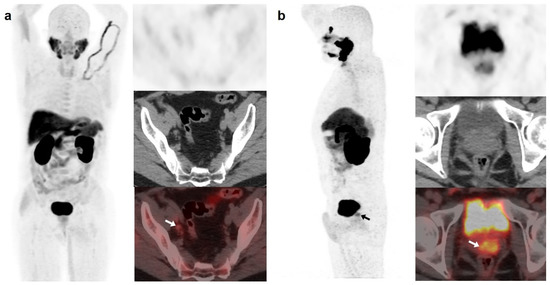

On the other hand, [18F]DCFPyL was positive alone in 48/89 (53.9%) patients, being oligometastatic in 25 (Figure 2). Five patients were exclusively positive with [18F]F-choline-PET/CT, and thus, [18F]DCFPyL down-staged [18F]F-choline results from positive to negative (3 follow-up, 1 biopsy (negative) and 1 ADT). [18F]DCFPyL up-staged 5/21 patients with oligometastatic disease on [18F]F-choline-PET/CT to polimetastatic disease after [18F]DCFPyL.

Figure 2.

67-year-old patient. Gleason 7 PCa treated with RP. First BCR treated with prostate fossa radiotherapy. Second BCR (PSA 0.63 ng/mL, PSAdt 8.6 months, PSAvel 0.04 ng/mL/month) scanned with [18F]F-choline (a) and [18F]DCFPyL PET/CT (b), time window of six days. Lymph nodes metastases (white arrows) were demonstrated only on [18F]DCFPyL scan, changing therapeutic management (escalation). Patient underwent lymph nodes SBRT. PSA level decreased.